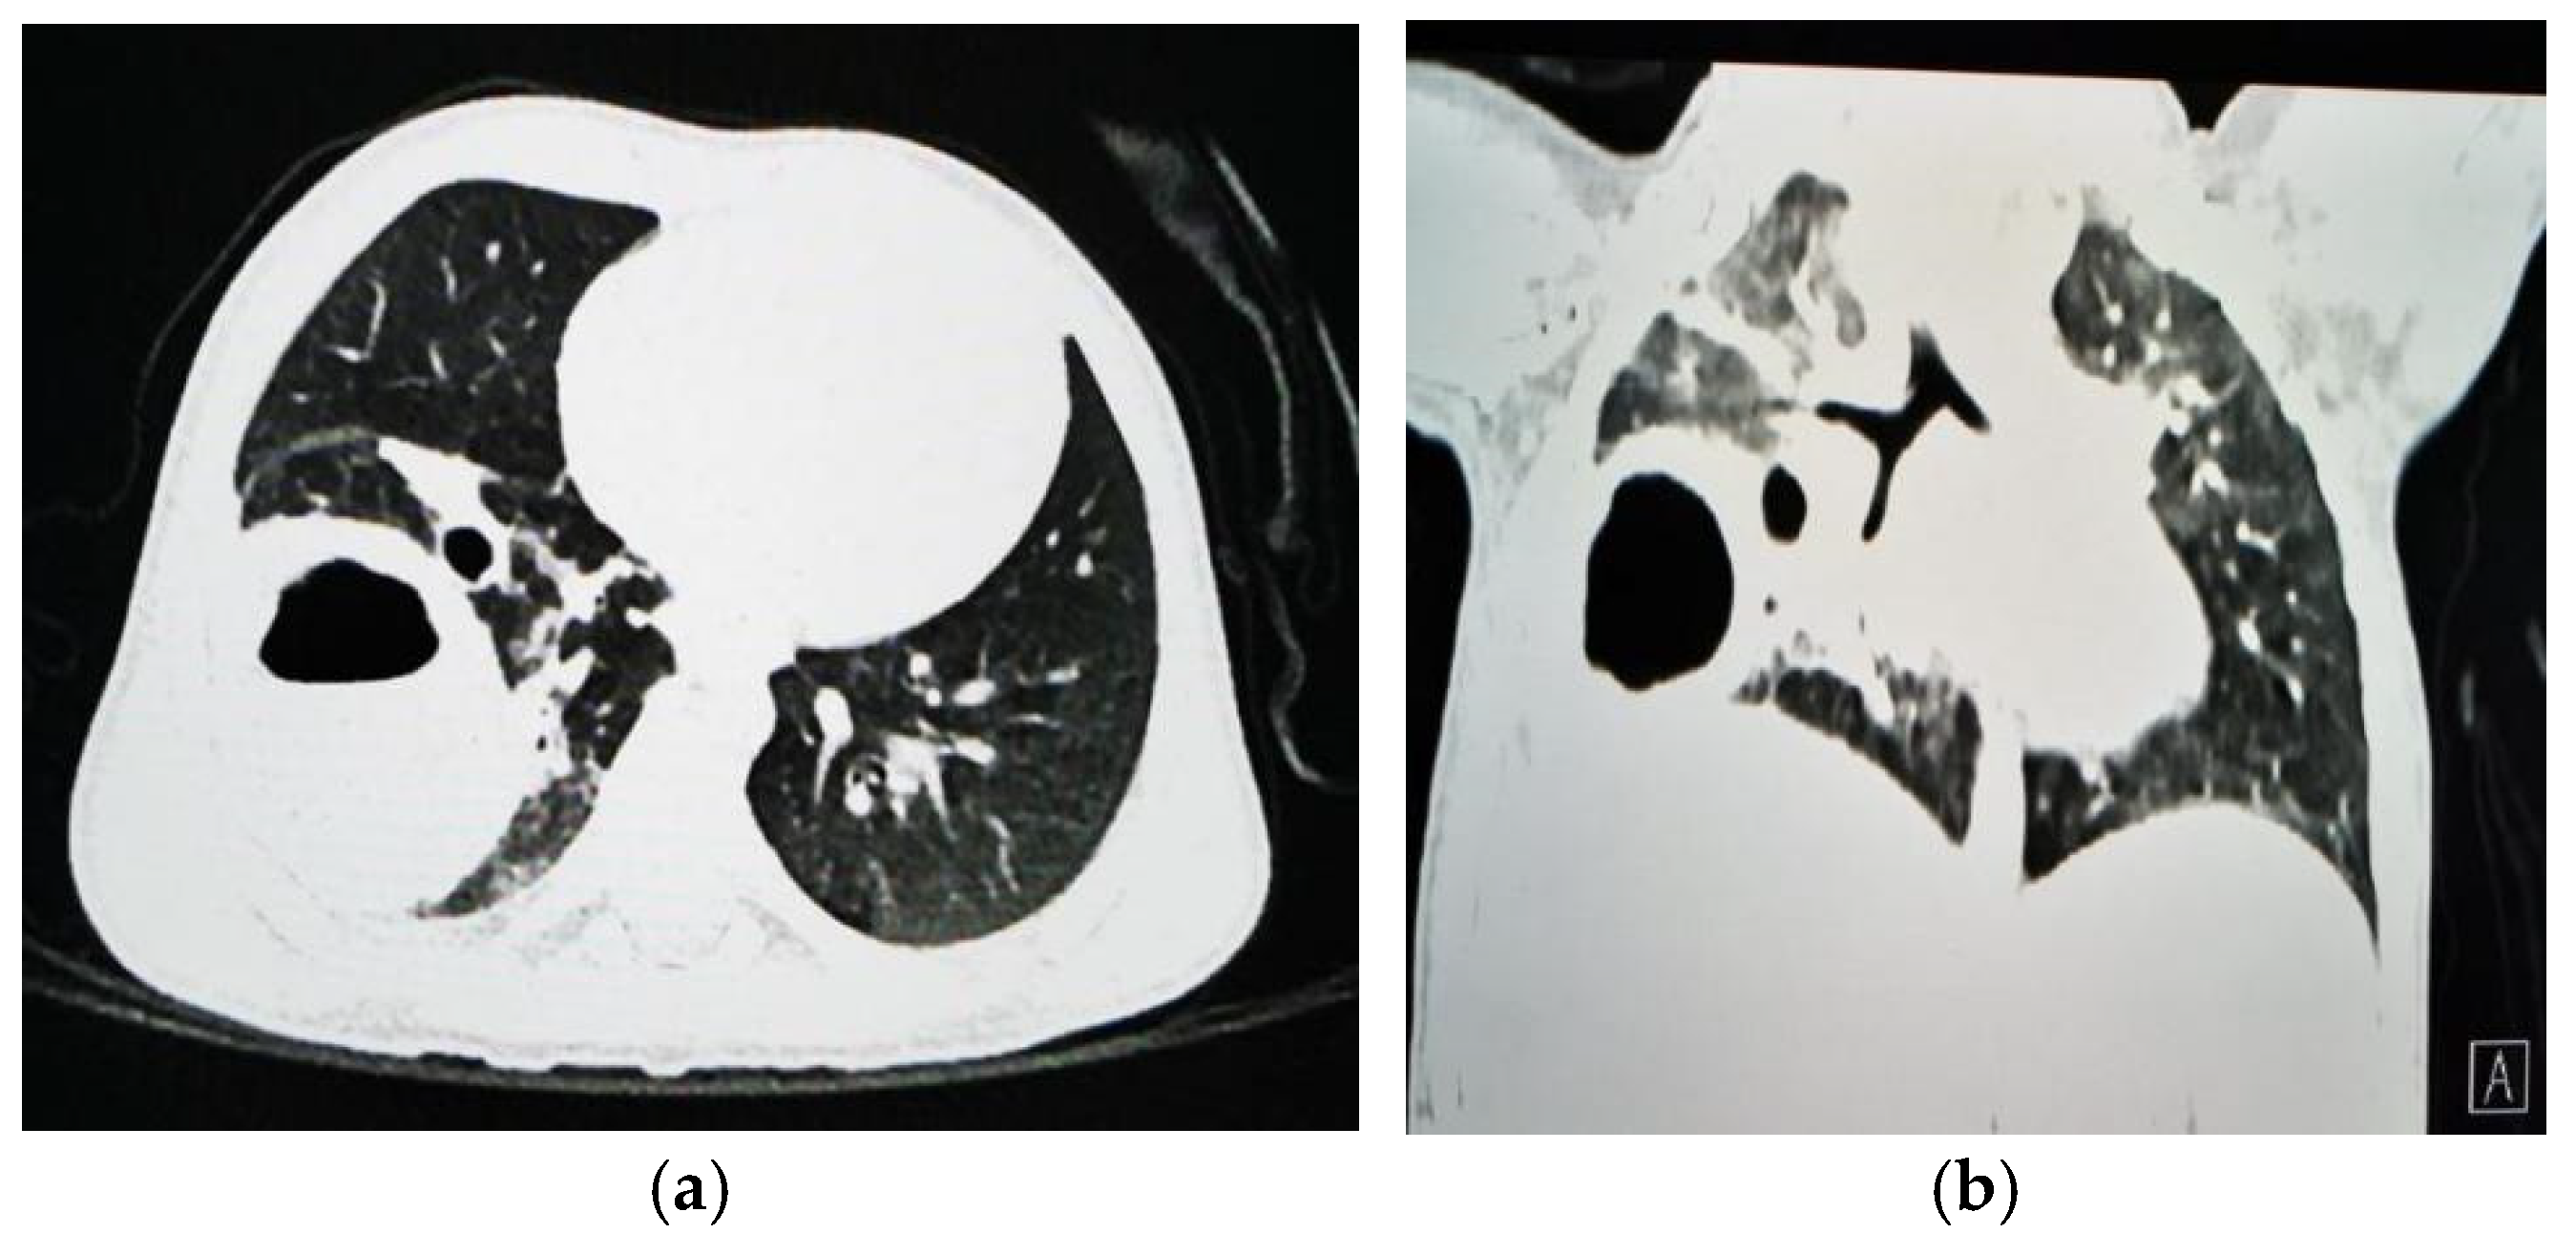

1.9.1. Case 1

1.9.2. Case 2